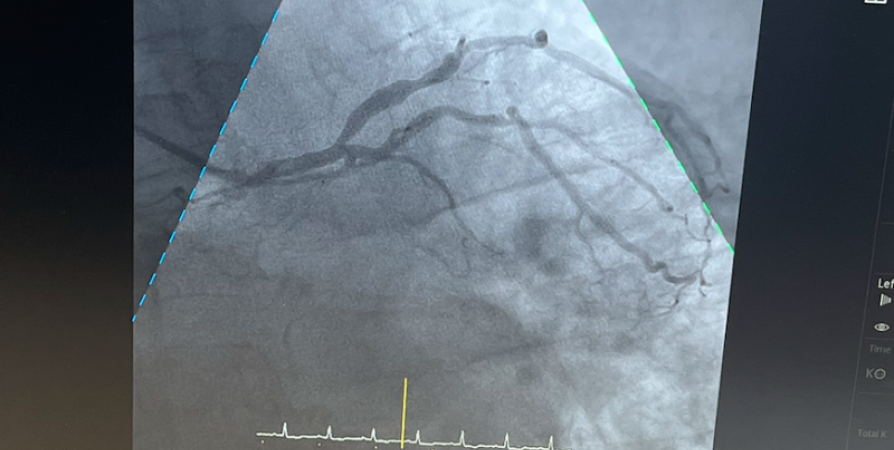

Врачи мурманского ММЦ имени Н.И.Пирогова ФМБА России провели первую балонную ангиопластику и имплантировали стент в общую подвздошную артерию.

Врачи  мурманского ММЦ имени Н.И.Пирогова ФМБА России  провели первую балонную ангиопластику и имплантировали стент в общую подвздошную артерию. Тем самым была достигнута полная реваскуляризация критически суженной артерии.

Напомним, что в центре открыли новую операционную, оснащенную современным ангиографом.

Специалисты центра уверены, что рентгенэндоваскулярная хирургия позволяет врачам максимально точно оценить состояние сосудов человека, обнаружить патологии и тромбы, принять правильное решение о тактике дальнейшего лечения пациента, а также снизить риски сердечно-сосудистых осложнений в будущем.

Ранее  Nord-News сообщало , что  в Мурманске были выполнены первые коронарографии, высокотехнологичные лечебно-диагностические вмешательства состоялись в новом операционном блоке на установленном ангиографе фирмы Philips Azurion 5F20.